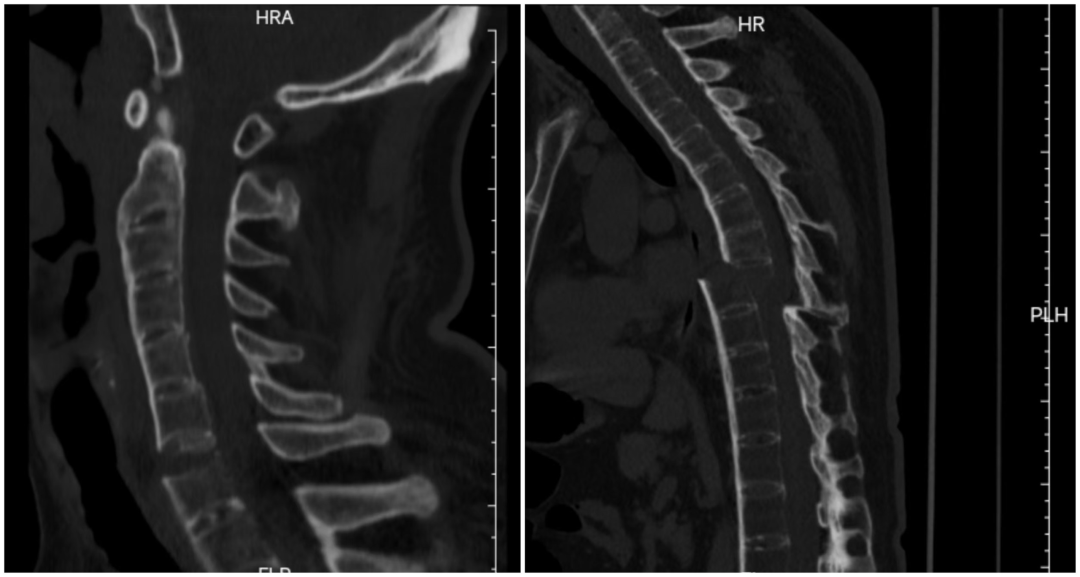

该患者因车祸导致颈椎横贯性损伤,颈椎前方极度不稳定,同时合并胸椎完全性骨折脱位,椎体漂浮、脊柱连续性中断。患者还有着多年的强直性脊柱炎病史,脊柱强直、骨质脆性高、稳定性极差,所幸入院时暂无明显神经压迫症状,四肢活动基本正常。然而,颈胸段脊柱序列已严重紊乱,麻醉后肌肉松弛,翻身等体位变化时稍有不慎,便可能引发脊髓严重受压,导致瘫痪甚至呼吸循环衰竭,手术难度与风险堪称脊柱外科手术的“珠穆朗玛峰”。

该患者因车祸导致颈椎横贯性损伤;同时合并胸椎完全性骨折脱位,椎体漂浮、脊柱连续性中断。